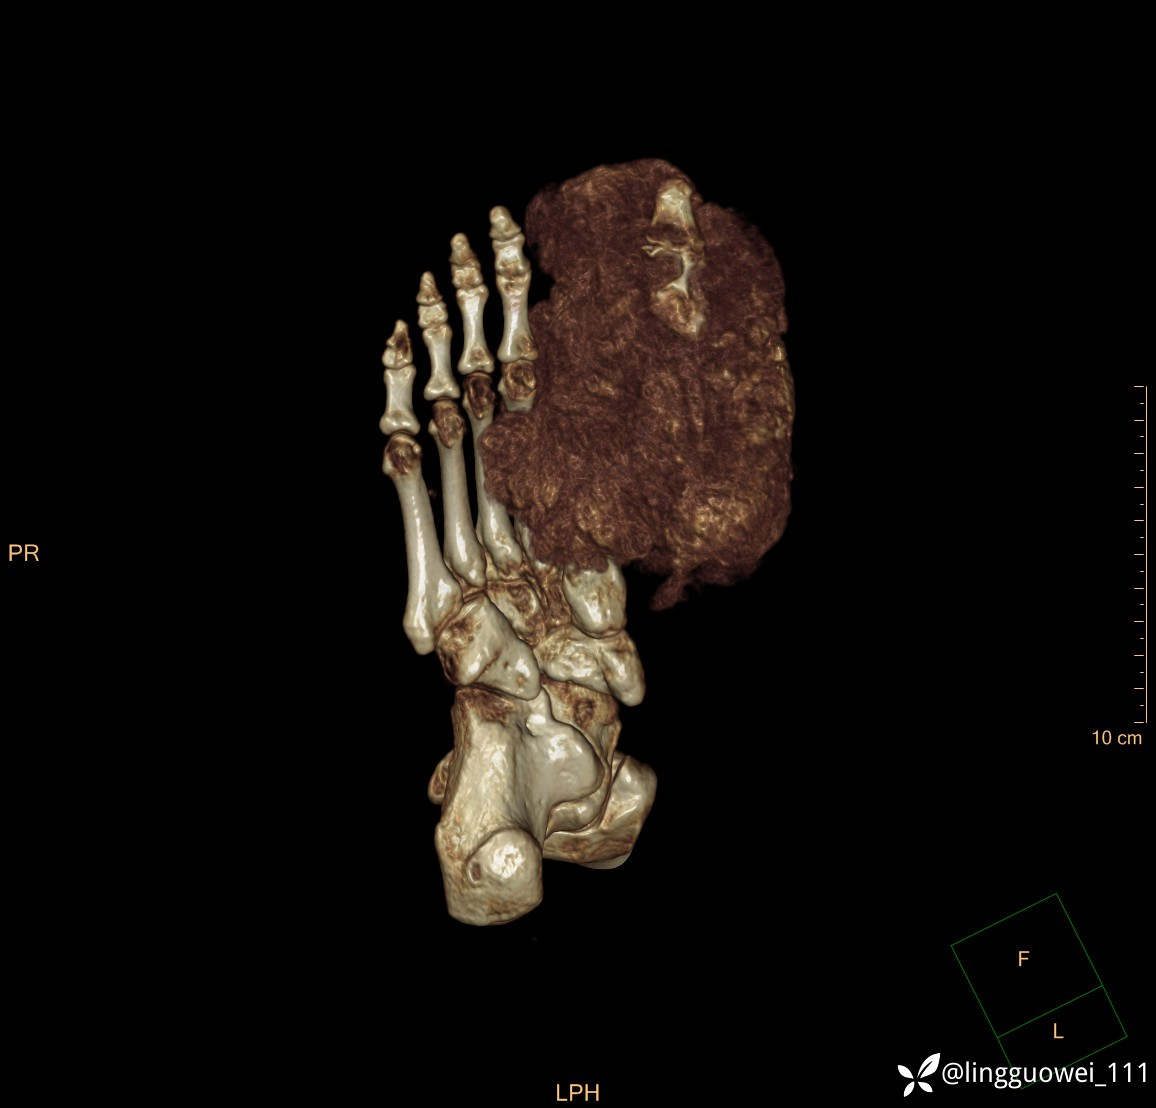

28岁男性,工作中遇到的足部最大的肿块,已补充临床资料。

28岁男性,足部肿块逐渐增大2年。能找到病因吗?

患者于2年余前高嘌呤饮食及大量饮酒后出现全身多处关节痛风石,以右足第一跖趾关节和右手为显,局部红肿热痛反复发作,自行口服药物后可缓解(药物可疑为强的松、双氯芬酸钠等,具体不详)。2年来右足痛风石明显增大,约10cm*5cm*15cm,局部红肿发热,3天前患者再次大量饮酒后痛风石顶部破溃,可见4cm*3cm皮损,较多白色豆渣样分泌物流出,为求进一步治疗来诊,门诊诊断为“右足痛风石破溃伴感染”, 收住院拟手术治疗,患者起病以来,无发热,精神佳、胃纳好、睡眠佳,大小便正常。

专科检查:右足外观畸形,足背部可见巨大痛风石形成,痛风石大小约10cm*5cm*15cm,局部皮肤红肿发热,痛风石顶部破溃,可见4cm*3cm皮损及白色豆渣样分泌物流出;痛风石界限清,质偏硬,局部触及波动感,无压痛,移动度差。右足踇趾及第2趾被痛风石压迫,关节活动受限。肢端血运、感觉无异常。 右手稍肿胀,2-5指背侧可见多发痛风石形成,最大者约花生米大小,皮肤完整未破溃,痛风石界限清,质偏硬,局部触及波动感,无压痛,移动度差。